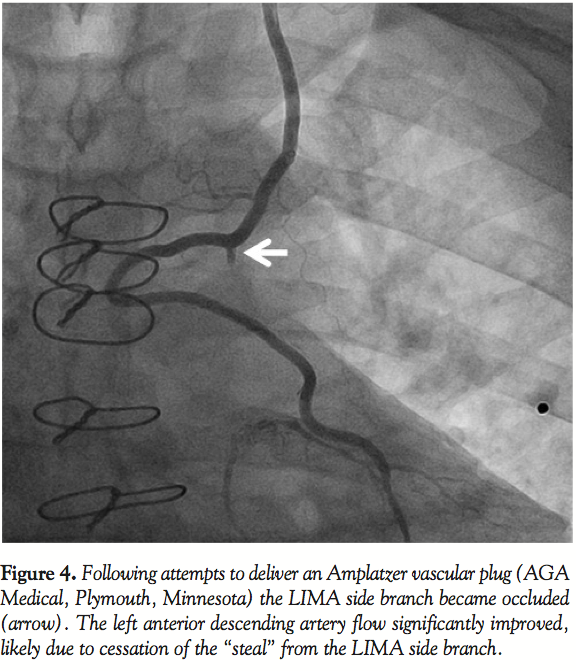

Left radial access was obtained with a 6 Fr sheath. The LIMA was wired with an Ironman wire (Abbott Vascular; Figure 2) and a Proxis catheter (St. Jude Medical) was inserted into the LIMA side branch (Figure 3). We attempted to deliver a 3 mm Amplatzer vascular plug (AGA Medical) through the Proxis catheter in the LIMA side branch, however significant resistance was encountered during delivery attempts. The device was partially deployed but in suboptimal location due to movement of the catheter during delivery. The vascular plug was recaptured and removed. LIMA angiography demonstrated side-branch occlusion. The LIMA side branch remained occluded after 15 minutes of observation. The patient had an uneventful recovery and has had no recurrent angina during 3 months of follow-up.

Discussion. Our case demonstrates an unconventional method for occluding a LIMA side branch by causing dissection of the side branch during attempts to place an Amplatzer vascular plug.

Our case highlights 3 important technical issues when attempting to close LIMA side branches. First, LIMA tortuosity may make access to the LIMA side branch challenging. Straightening of the tortuosity through wire and catheter insertion may result in slow flow or complete cessation of flow, which can hinder visualization of the target vessel14 and impede delivery of the occlusive device. In our patient, difficulty in delivery of the Amplatzer vascular plug likely contributed to LIMA side-branch dissection and occlusion. Use of fixed landmarks, such as surgical clips could aid in delivering the occlusion device to the desired location. Second, a long distance may exist between the LIMA ostium and the side-branch ostium, as in our case, further complicating delivery of an Amplatzer plug. In such circumstances, use of radial access or using coils that require a smaller delivery microcatheter may be advantageous. Third, it might be safest to insert a guidewire into the LIMA past the ostium of the side branch to allow prompt treatment of the LIMA if inadvertent injury occurs during attempts to close the side branch.